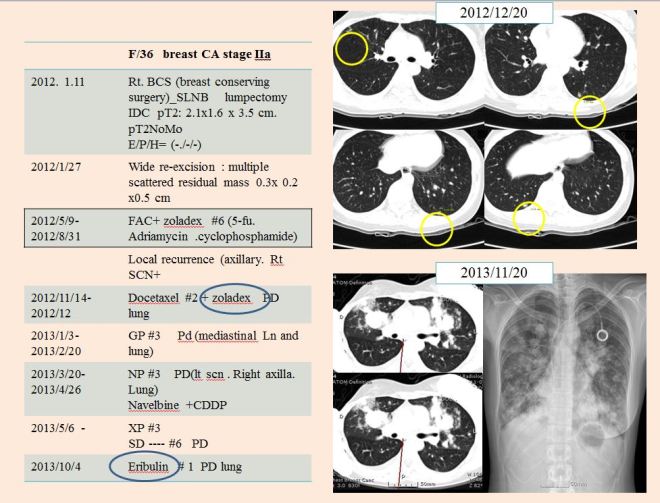

history.

• 2016.8.11 – 유방암 대략 3cm 우측 유방에 발견

• S 병원에서 수술. 유방암 stage는 2기A로 판명

• 2016.9월부터 2017.1월까지 AC #4 시행함

• 2017.1부터 주마다 paclitaxel 시행함. zoladex도 사용함

• 2017.2.22 7차 항암 이후 손발저림이 심해서 리리카를 복용하고 어지러움증과 불면 지속

• 2017.3.29 paclitaxel #12 차 종료

• CT상 폐전이 발견. 방사선치료 예정 있었으나 폐전이 발견돼 중지

• 2017.3.31 CT chest – 다발적 폐전이와 종격동 림프절전이 발견

• 2017.3.31- 2017.5.15까지 – gemcitabine+cisplatin 결합요법 시행

• 3차까지는 호전반응을 보이다가 4차(5/15) 이후에 chest상 종양이 약간 커진 것을 발견하고 이 요법을 중지함

• 2017.6.8 안양 S 병원으로 이전 치료

• 2017.6.8 할라벤 1차 시행함

• 2017.6.21 – 제로다와 나벨빈 1차 시행함

• 2017.7.3 – 티센트릭 시행함

• 2017.7.13 반룡인수한의원 내원

• 이후 응급으로 서울대로 전원. 일주일 내 사망(2017.7.28일 사망 확인함).